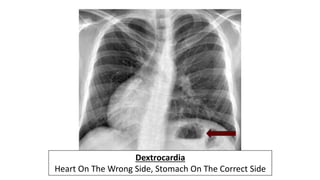

Dextrocardia

Heart On The Wrong Side, Stomach On The Correct Side